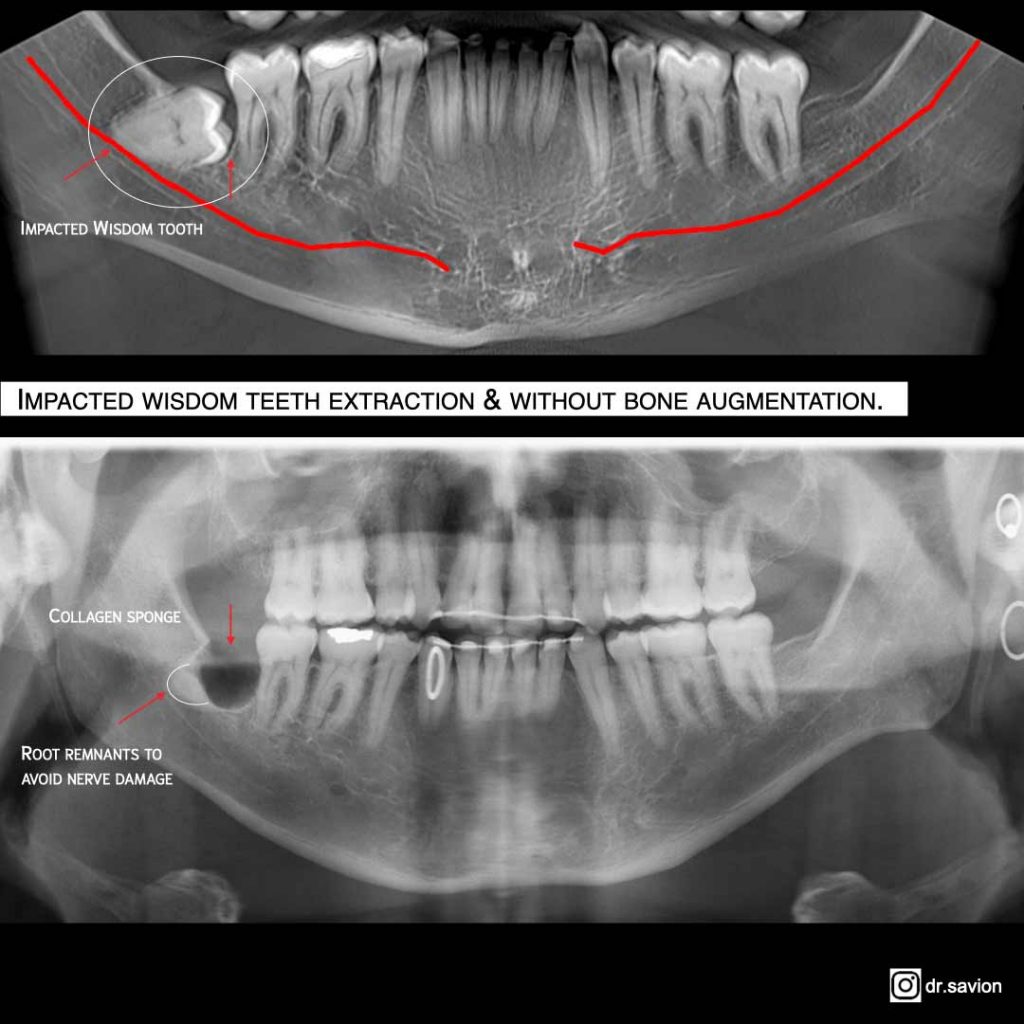

An impacted wisdom tooth refers to a tooth that fails to fully erupt or emerges only partially into the oral cavity, often in a mesial or distal position. This creates pressure on surrounding teeth and frequently results in severe pain, swelling, and periodontal pocket formation.

- Impacted Wisdom Teeth: This represents the most prevalent complication. When wisdom teeth lack sufficient space in the jaw to erupt properly, they become trapped beneath the gum line or jawbone, leading to pain, swelling, and infection. Impacted wisdom teeth can also damage adjacent teeth, causing decay and infection. In certain cases, surgical extraction of the impacted wisdom tooth may be necessary to prevent further complications.

- Bone Removal: If the tooth is partially or completely impacted, the oral surgeon may need to remove some of the bone surrounding the tooth to gain access and safely remove the tooth.

- Sectioning: If the tooth is too large or deeply rooted to be removed whole, the doctor may need to section the tooth into smaller pieces to facilitate removal.

- Extraction: Once the tooth is properly exposed, the doctor carefully extracts the tooth from its socket.

- Nerve Damage: In rare cases, nerves in the jaw or mouth may be damaged during wisdom tooth extraction, leading to numbness or tingling in the lips, tongue, or cheeks. This is usually temporary but can be permanent in rare instances.